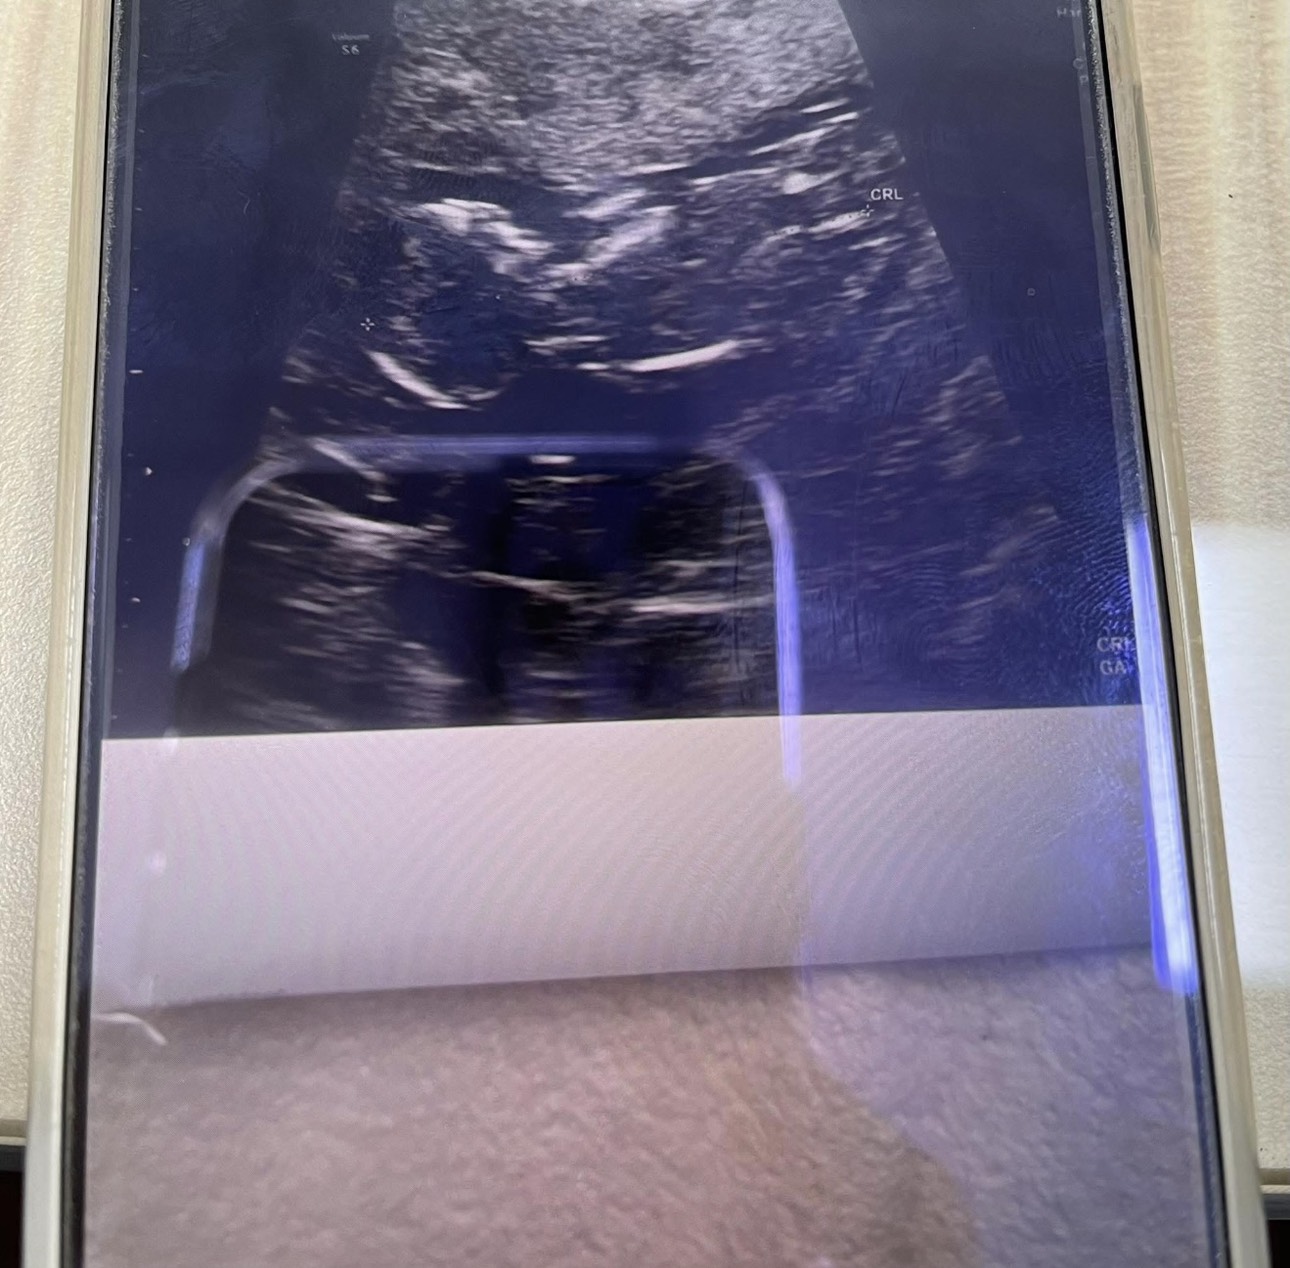

給予適合中藥治療後,H小姐恢復規律排卵,計畫性自然受孕成功,目前持續服用中藥安胎,胎兒已經超過三個月大,穩定成長中。

圖片為患者懷孕時分享給蘇醫師的超音波檢查照片。